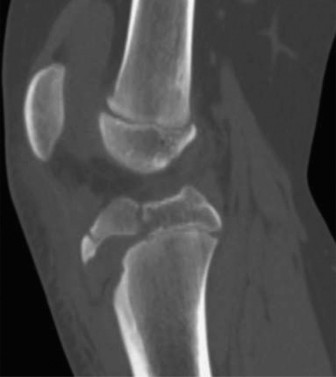

Risk of overgrowth in children who sustain diaphyseal femur fractures? CASE 9 A 14-year-old boy is brought to the ER with complaints of right knee pain after he was injured playing basketball. X-rays and a CT scan (CT Shown in Fig. 10–12) were done at an outside hospital and he was transferred to you for care.

Figure 10–12

The correct answer is (B). Tibial tubercle fractures occur more commonly in adolescents with a history of Osgood–Schlatter disease, but a causal relationship has yet to be demonstrated. Osgood–Schlatter disease is an overuse injury caused by repetitive strain across the tibial tubercle apophysis. Tibial tubercle avulsion fractures are not known to occur more commonly in young people who have patellofemoral syndrome (anterior knee pain associated with overuse), Sinding-Larsen–Johansson syndrome (a condition similar to Osgood–Schlatter, affects the lower pole of the patella, not the tibial tubercle and therefore not associated with tibial tubercle fractures), nor in people who have inflammation of the patella tendon. Therefore, choices A, C and D are not correct.